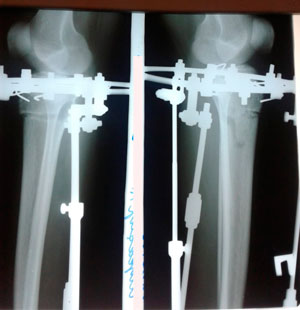

Дата операции - 05.07.2019г.

Дата снятия аппаратов - 13.09.2019.

Срок сращения - 71 день.